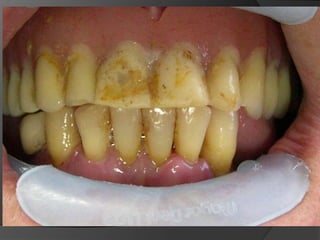

fundamentos de periodoncia en prótesis fijaEl éxito de una prótesis no es medida solamente en el acto de la cementación, sino también a lo largo del tiempo, por estar integrada y en armonía con la estética, tejidos pulpares, tejidos periodontales, músculos y articulación temporomandibular.1

fundamentos de periodoncia en rehabilitaciónEs incuestionable que la salud del periodonto deba ser restablecida antes de cualquier tratamiento restauradorEl paciente es responsable en gran medida del mantenimiento de su salud bucal

fundamentos de periodoncia en prótesis fijaContornos y Texturas de las RestauracionesEn cualquier restauración protésica, temporal o definitiva, el subcontorno y, principalmente, el sobrecontorno, deben ser evitados.3

El sobrecontorno, es un factor retentivo de placa. Las fibras circunferenciales de la encía marginal se desgarran y los tejidos gingivales buscan la migración apical

El subcontorno desencadena una hiperplasia gingival e induce a la impactación de alimentos en el surco gingival